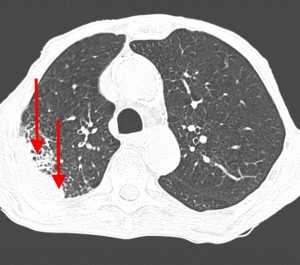

Вторичные узлы гематогенного характера чаще всего имеют ровные края, четкие контуры и однородную структуру. Возможны изменения структуры опухоли вследствие кровоизлияния в паренхиму, обызвествлений, некроза центральной части узла, а также рубцов. Края узла могут стать нечеткими, расплывчатыми, если опухоль провоцирует отек легочной паренхимы, либо «лучистыми», если имеет место опухолевый лимфангиит.

Слева - рак почки с метастазами в легкие, прогноз в данном случае неблагоприятный ввиду метастатического плеврита и дыхательной недостаточности. Определяются очаги с обеих сторон. Справа - мелко- и среднеочаговая диссеминация при раке печени.

Множественные гематогенные вторичные узлы при раке почки, компьютерная томография (КТ).